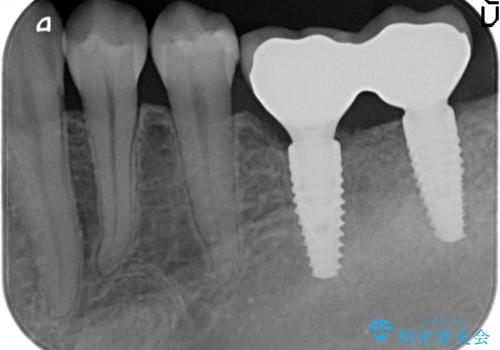

- 90万円(ストローマンインプラント・骨造成・チタンカスタムアバットメント・ジルコニアクラウン×2)費用は治療当時の料金となります

インプラントを用いて機能回復を行うことで、奥歯がしっかりと噛めるようになります。

周囲に骨があることでより長期的な予後を見込むことができます。